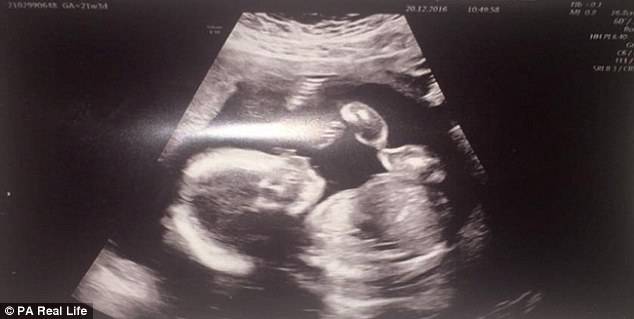

Quando Amber Fullarton era alla 20° settimana di gravidanza, durante una visita di routine, ha scoperto che il cuore di sua figlia non si stava sviluppando correttamente.

La diagnosi del cardiologo era molto pesante: la Sindrome del cuore sinistro ipoplastico.